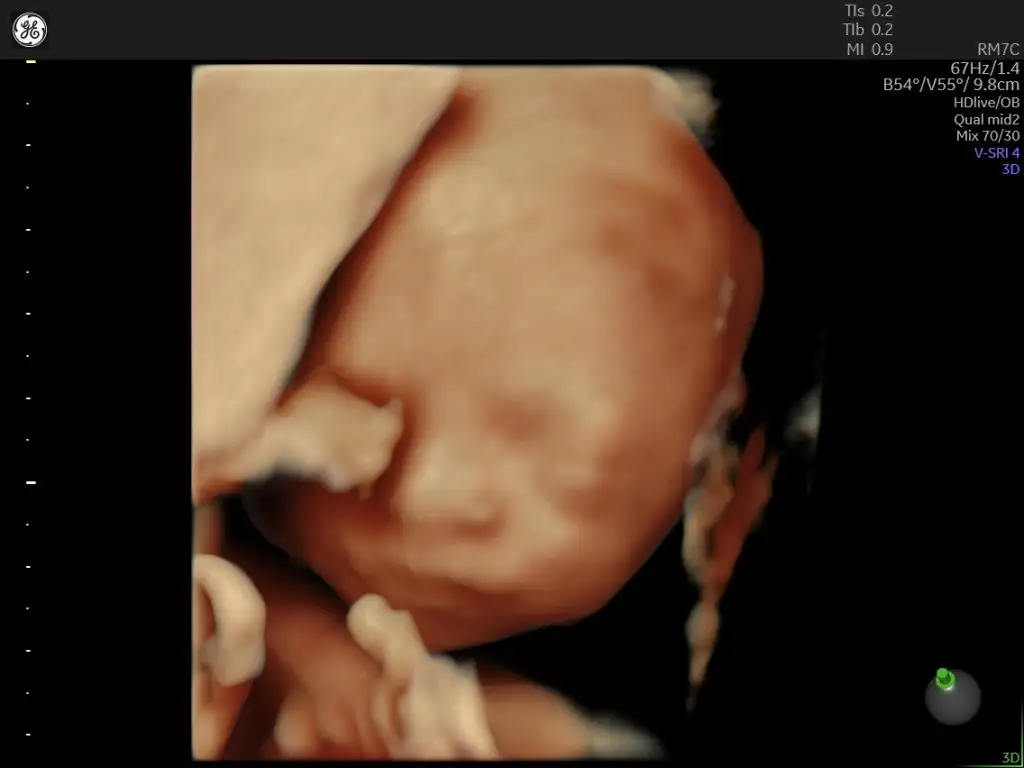

Yaaa çok tatlı maşallah ömrü bahtı güzel olsun inşallahMerhaba herkese. Bugün benim de detaylı ultasonum vardı. 22+5 olduk bugün. Çok kısa sürdü benim detaylı 20-25 dk kadar daha uzun bekliyordum ama bir sorun yok dedi ondan kısa sürmüştür diye düşünmek istiyorum. Bir de ilk defa yüzünü gördük kızımızınsizle de paylaşmak istedim

Çok teşekkürlerYaaa çok tatlı maşallah ömrü bahtı güzel olsun inşallahgüzel foto vermiş size bebiş

MaşaAllah ne güzel poz vermiş, sağlıkla kucağınıza alın kızınızıMerhaba herkese. Bugün benim de detaylı ultasonum vardı. 22+5 olduk bugün. Çok kısa sürdü benim detaylı 20-25 dk kadar daha uzun bekliyordum ama bir sorun yok dedi ondan kısa sürmüştür diye düşünmek istiyorum. Bir de ilk defa yüzünü gördük kızımızınsizle de paylaşmak istedim